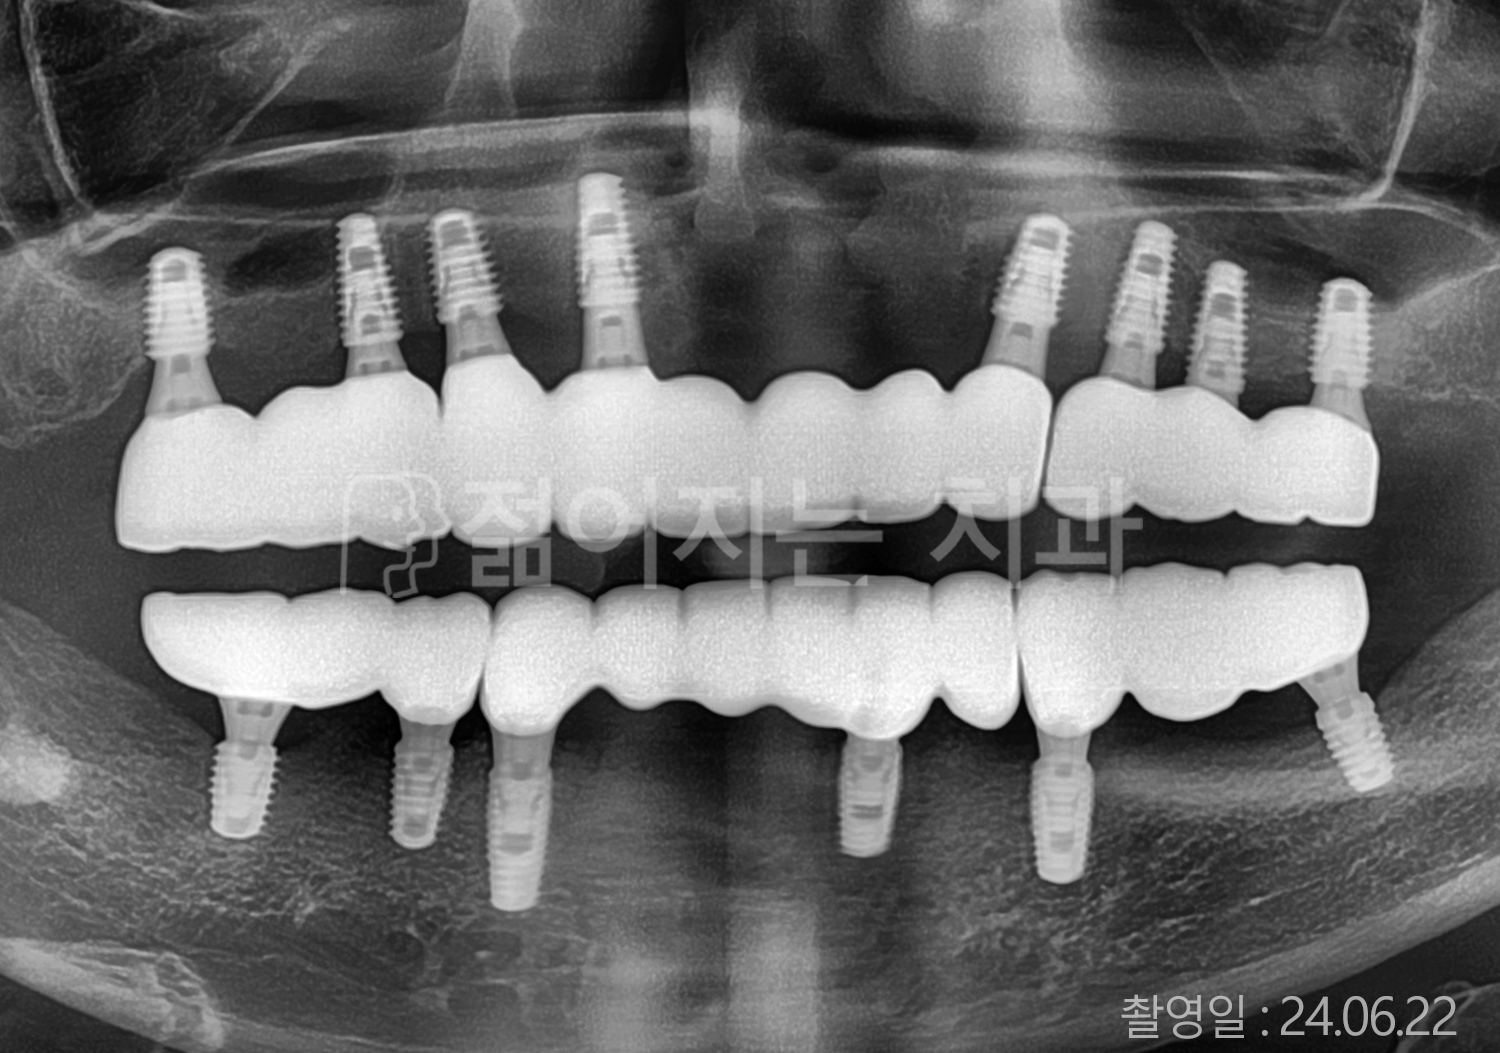

• 60대 전체치아 10개 이상 임플란트